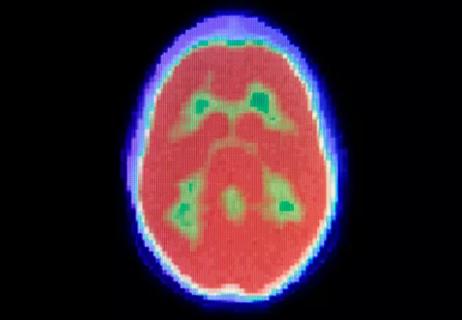

Brain scanning

August 31, 2022/Cancer/Research

Investigational PET Imaging Agent Being Explored as a Predictive Biomarker For Response to Standard Chemotherapies

Pilot Study at Cleveland Clinic is Testing Feasibility and Biodistribution